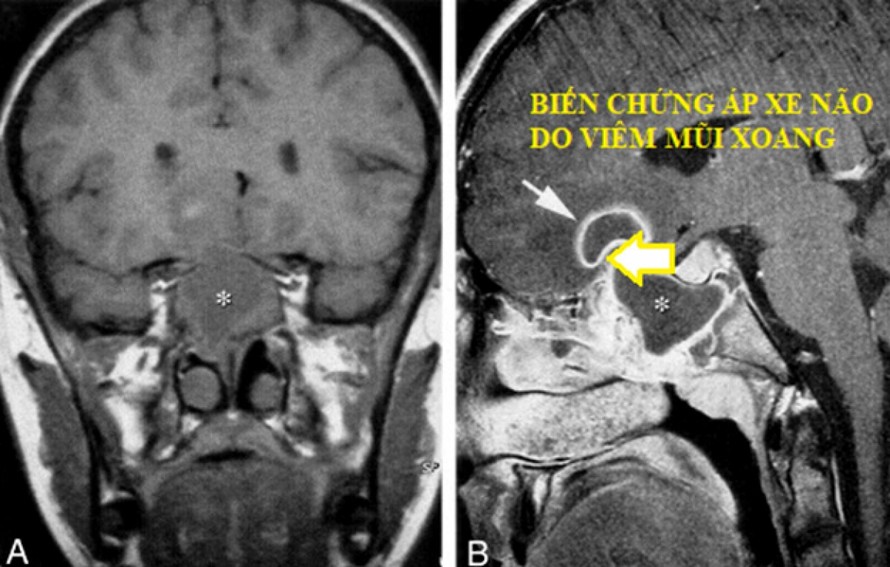

Chẳng hạn như biến chứng áp xe não là một trong những biến chứng có thể gây nguy hiểm đến tính mạng do viêm mũi xoang. Với biểu hiện sau khi sốt, chảy mũi, ngạt tắc mũi…, bệnh nhân sẽ xuất hiện những cơn đau đầu dữ dội, có vùng đau rõ ràng thường ở vùng trán, kèm theo nôn vọt, tinh thần trì trệ, có thể hôn mê. Lúc này bác sĩ khám sẽ thấy niêm mạc mũi xoang sung huyết, các khe mũi có dịch mủ… Hình ảnh chụp cộng hưởng từ thấy có viêm xoang và ổ áp xe não kế cận ổ viên xoang. Bác sĩ sẽ phải xử trí dẫn lưu ổ áp xe và điều trị bằng kháng sinh toàn thân cũng như điều trị thuốc tại mũi xoang.